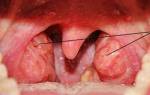

Тем, кто сталкивался с белыми гнойничками на миндалинах, несложно узнать их симптомы. Но если вы не знаете, как они выглядят, то можно посмотреть эти образования на фото.

- если вы обнаружили в глубине складок миндалин белые пятнышки, — это значит, что там гнойные пробки, которые нужно немедленно лечить.